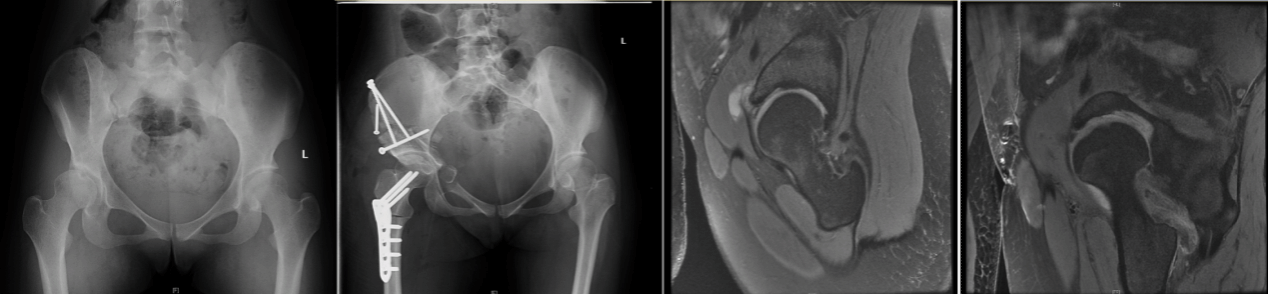

近年来我所已开展针对成人髋关节发育不良的保髋治疗。目前髋关节组已开展髋臼周围截骨术、股骨去旋转截骨术近五十例,包括专业运动员3例,近期随访效果满意。同时,髋关节组在国内率先开展了髋关节镜联合髋臼周围截骨术,首先利用髋关节镜下将关节内的盂唇及软骨损伤进行修复,然后通过髋臼周围截骨手术改善患者的髋臼覆盖情况。本手术方式可以更好地提高患者的手术疗效。这丰富了我所髋关节疾病的治疗手段,极大推动了髋关节专科的学科发展。